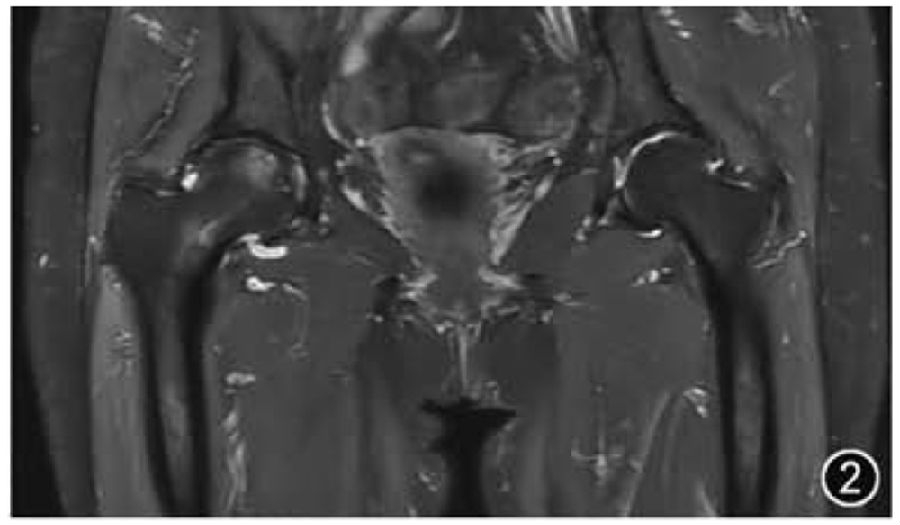

1.OA:OA是髋关节最常见疾病,是关节软骨、软骨下骨和软组织退化的结果。MRI有助于早期识别髋关节OA,并可用于随访评估。一般来说,髋关节OA由医师诊断,分为轻度、中度和重度进行报告即可,其他更详细的基于MRI的髋关节评分系统大多用于研究而非临床常规报告内容。在髋关节OA中重点需要关注的常见相关影像学特征应包括:髋臼及股骨头颈等骨质形态、骨质增生及骨赘、软骨及软骨下是否有囊变及水肿、髋臼盂唇损伤、关节积液、滑膜炎及游离体等。需要注意的是,关节软骨变薄的评估通过医师目测即可而无需测量(图2)。

图2 双侧髋关节骨关节炎MRI图像。冠状面T2WI示双侧髋关节间隙狭窄,骨质增生,右侧股骨头可见关节面下斑片状骨髓水肿